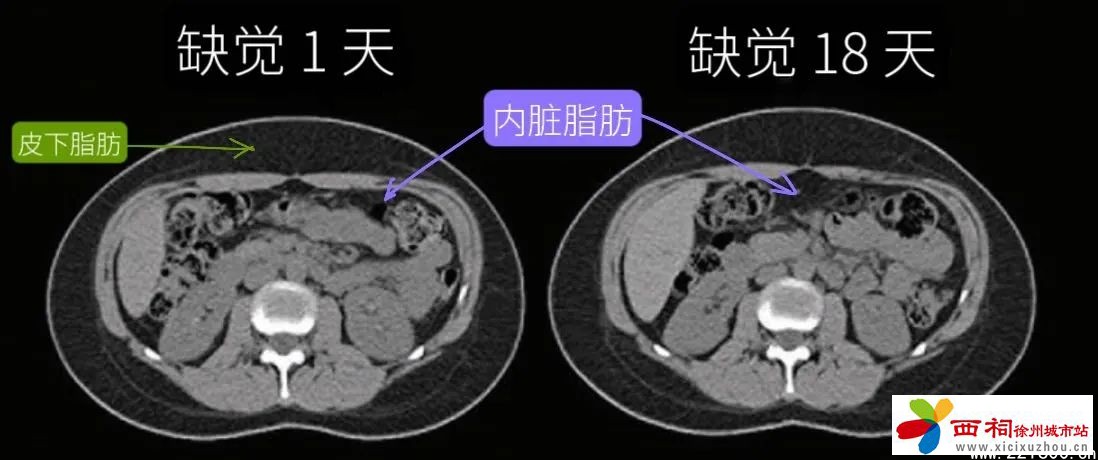

02缺觉长出来的脂肪可能是“内脏脂肪”

都是胖肚子,却有胖“皮下”和胖“内脏”的区别。

科学家在发现“缺觉会导致肚子长胖”后,又进一步分析了内脏脂肪的占比,得到了这样的结论:

• 睡饱睡足、不缺觉的人,即使不小心吃多、稍稍发胖一些,也主要是存在皮下,内脏脂肪面积没有出现明显增加。

• 反观缺觉的人,不仅更容易胖,内脏脂肪面积也足足增加了11%,就算是缺觉后立马补觉也无济于事。

缺觉时脂肪存储机制变化,更容易把脂肪转移到肚子内部,变成“内脏脂肪”,包围各大内脏器官,损伤心血管、影响身体代谢。